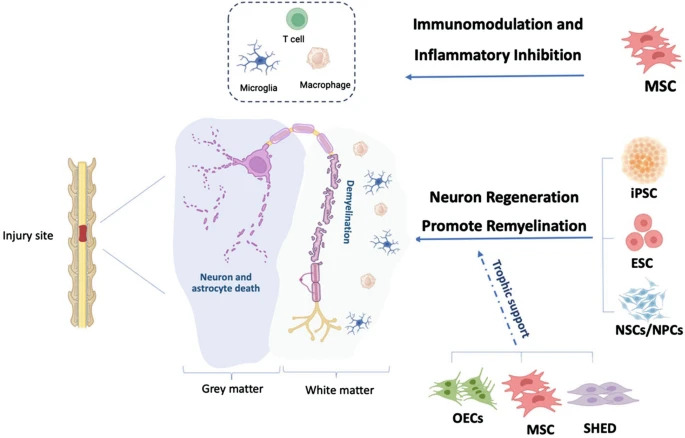

由于干細胞固有的獨特再生能力,細胞療法有望促進丟失神經元的替換、調節免疫反應、促進軸突再生、促進受損軸突的髓鞘再生,并建立有利于功能恢復的環境。目前正在研究用于TSCI治療的不同類型干細胞,包括胚胎干細胞(ESC)、誘導多能干細胞(iPSC)、間充質基質/干細胞(MSC)和神經干細胞/祖細胞(NSPC)(圖3)。

免疫調節

神經炎癥被認為是繼發性損傷的關鍵因素,直接影響TSCI治療的療效。研究表明,初始炎癥反應能夠清除細胞碎片并增強神經營養因子,從而在支持性微環境中促進神經修復和重塑。然而,持續的炎癥可能導致炎癥細胞因子、蛋白水解酶、基質金屬蛋白酶和活性氧 (ROS) 的釋放,最終導致鄰近健康細胞凋亡、軸突斷裂和神經元脫髓鞘。

多項研究表明,骨髓間充質干細胞 (BMMSC) 可減輕脊髓損傷后的炎癥反應。BMMSC顯著提高了TSCI 環境中抗炎細胞因子IL-4和IL-13的表達水平,同時降低了促炎細胞因子TNF-α和IL-6的表達水平。這些炎癥因子的變化與浸潤巨噬細胞表型從M1轉變為M2密切相關。BMMSC顯著降低了TGF-β1/Smads 信號通路中 TGF-β1、Smad2和磷酸化 (p)-Smad2的表達,從而減輕了TSCI部位的炎癥。

神經再生

干細胞的多向分化與細胞替代

干細胞通過定向分化替代丟失的神經細胞,重建神經連接:

胚胎干細胞(ESC)?分化為神經元、少突膠質細胞等,直接替換受損組織,其衍生神經祖細胞可形成多層外源性髓鞘,促進脫髓鞘軸突的再髓鞘化;

神經干細胞/祖細胞(NSC/NPC)?在損傷區分化為成熟神經元(NeuN?、Tuj1?)、運動神經元(ChAT?)及膠質細胞,延伸長距離軸突跨越損傷區;

誘導多能干細胞衍生NSC(iPSC-NSC)?經γ-分泌酶抑制劑(GSI)預處理后,分化為功能性神經元(Hu?)、少突膠質細胞(APC?),并顯著增加血清素能纖維(5HT?)再生。